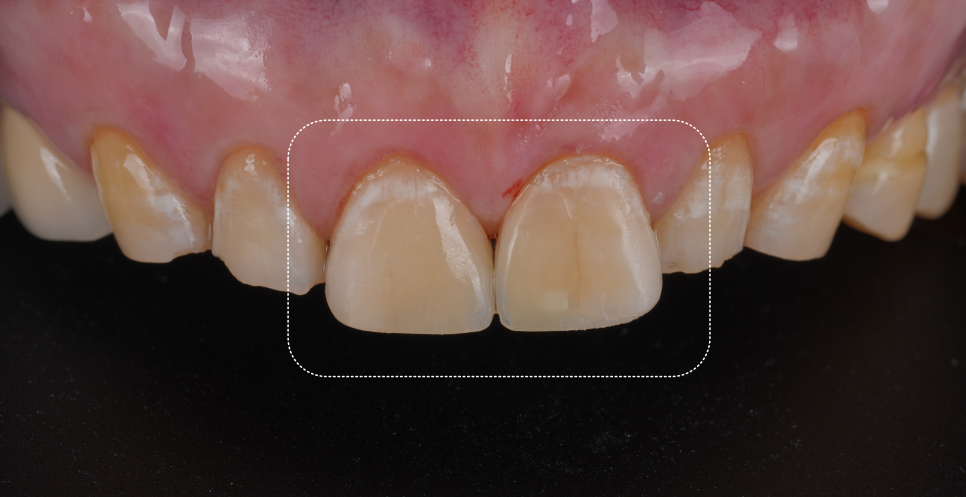

필요한 양만 다듬어서 치아 색상을 확인했습니다.

촬영일 : 251020

보철이 만족스럽게 제작됐더라고요.

환자분께서도 색상과 모양도 마음에 드신다고 하셔서 임시 접착제로 1주일 간 써보고 경과를 보기로 했습니다.

1주 뒤, 불편한 점이 없으시다고 하셔서 최종 접착을 했어요.

촬영일 : 251029